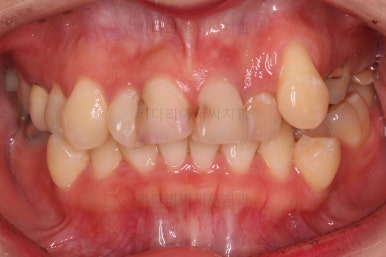

앞니 심미보철까지 마무리 되었습니다.

부산교정 전후 비교해 볼게요.

양호했던 입매는 거의 그대로 유지했고, 웃을 때 드러나는 치열과 치아의 모습은 너무나도 좋아졌죠.

교정치료에 충치, 심미보철까지 한다고 부산교정 기간이 오래 걸렸지만 긴 기간동안 참 고생 많이 하셨습니다.